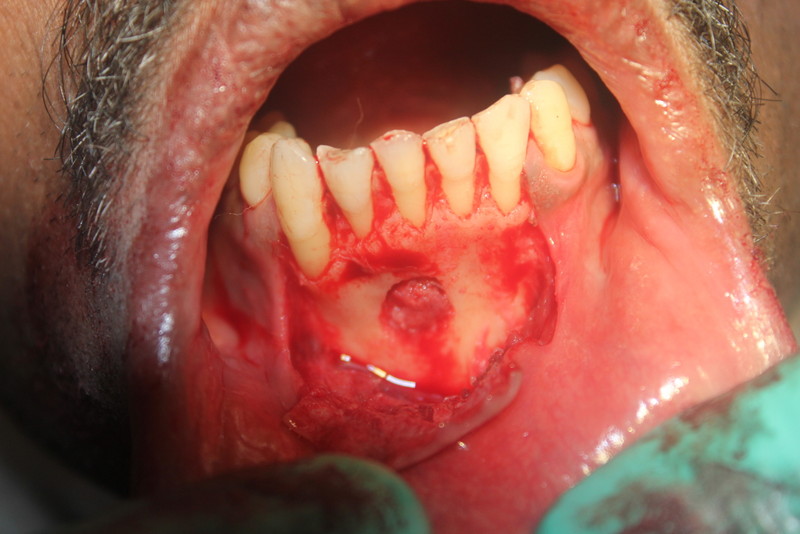

Dental Implants and Autogenous Bone Grafting